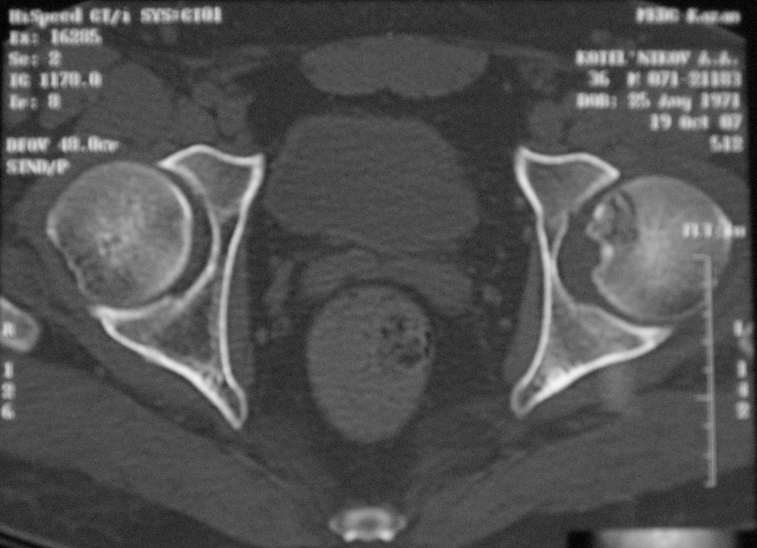

Молодой человек, 37л. Начало заболевания сентябрь 2007, резкие боли в области лев. тазобедренного сустава, повышение температуры до 39 гр., в течение недели, лабораторные данные: лейкоцитоз со сдвигом влево. Посев крови на стерильность возбудителя не выявил. По данным Рг, РКТ выставлен диагноз: Левосторонний коксит? Асептический некроз? Проводилось лечение: цефсон в/в неделю, иммобилизация кокситной повязкой 1 мес. Обратился повторно 10 дней назад с жалобами на сильные боли в левом тазобедренном суставе, белая кровь – нормограмма, СОЭ 46 мм/ч. На сегодняшний день: болей не отмечает. Лаб.данные: белая кровь – нормограмма, СОЭ 30 мм/ч. Рентген и РКТ прилагаем.

Рассмотреная тактика лечения: операционная биопсия.

При отрицательных данных за коксит - диагноз асептический некроз - эндопротезирование

При положительных данных за коксит какие методы могут быть использованы?

Правомочна ли резекция головки, установка спейсера, тотальное эндопротезирование.

На какой срок устанавливать спейсер? Имеет ли здесь право как методы лечения сегметарная резекция головки, артродезирование тазобедренного сустава?